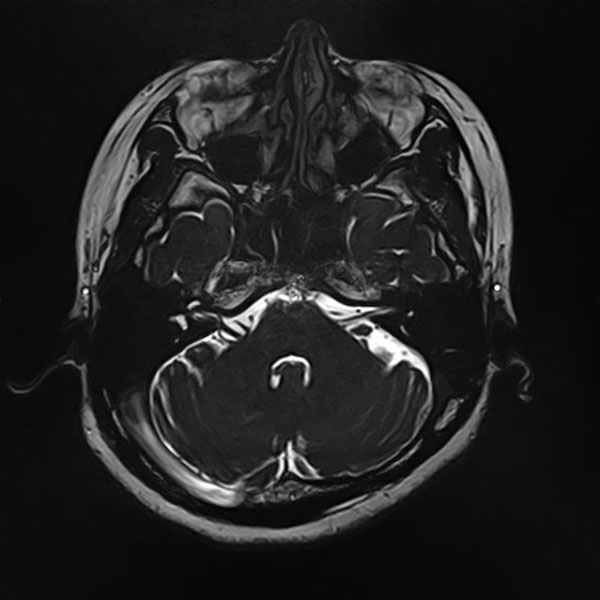

手術前

(MR1)